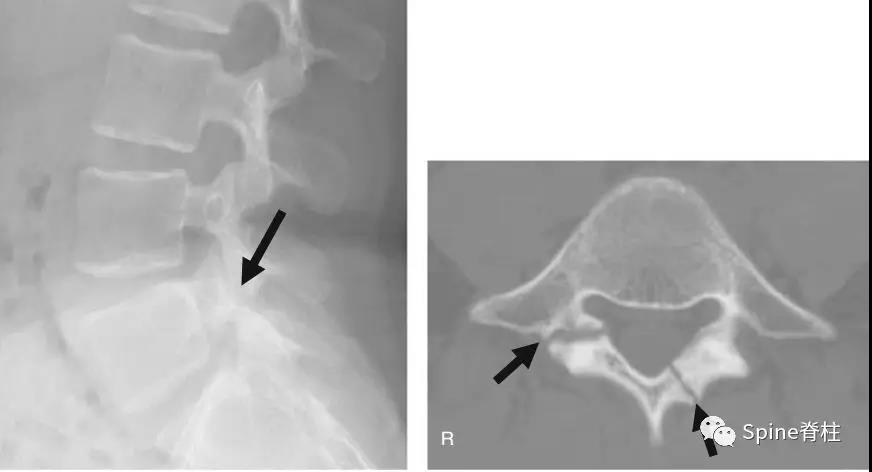

2003年发表在Am J Sports Med杂志(IF=6.20)上的病例报道,很好的阐述了峡部裂和椎弓根裂的变化。描述一个17岁的棒球运动员,运动后腰痛1月余,随访的辅助检查提示相同椎体水平出现的3个连续性应力性骨折:第一次为左侧峡部,第二次为右侧椎弓根,第三次为右侧峡部。

图:6个月复查可见右侧椎弓根裂已愈合(单箭头),但出现右侧峡部裂(双箭头)